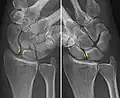

X-ray images indicate scapholunate ligament instability when the scapholunate distance is more than 3 mm, which is called scapholunate dissociation.[7] A static scapholunate instability is generally readily visible, but a dynamic scapholunate instability can only be seen radiographically in certain wrist positions or under certain loading conditions, such as when clenching the wrist, or loading the wrist in ulnar deviation.[6]

Dynamic instability: Increased scapholunate distance (between yellow lines) upon ulnar deviation of the wrist, but not otherwise. -